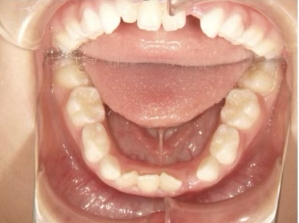

治療中④ 小4:10y1m

左上3が八重歯で萌出中